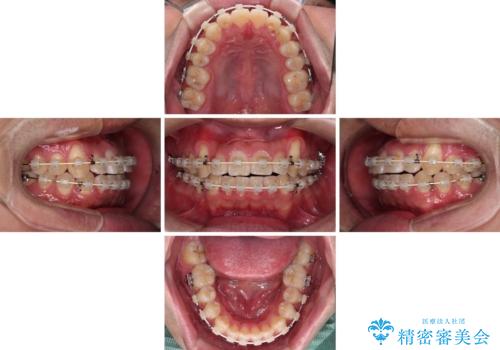

- 矯正装置

- 審美装置

- 2年6ヶ月

- 30回以上